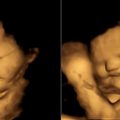

Anne karnındaki bebekler de lahana sevmiyor

Son bir araştırmaya göre anne karnındaki bebekler dahi tat uyaranlarına tepki gösteriyorlar. Fetüsler annelerinin yediklerini amniyotik sıvıdan algılıyorlar. Araştırmacılar farklı yiyeceklere gösteril...